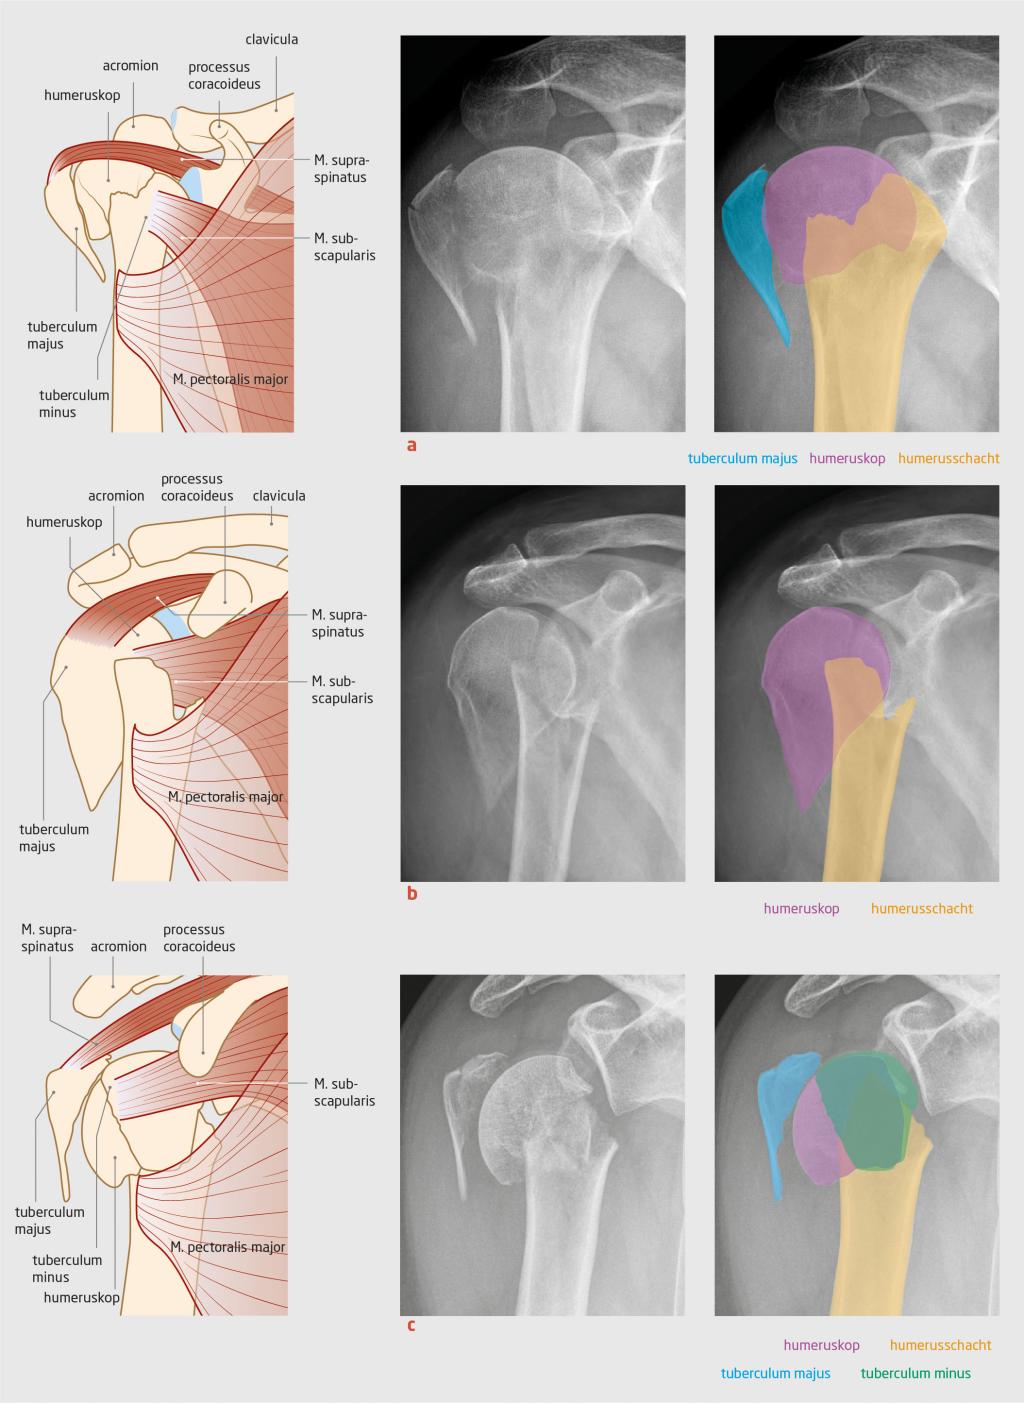

Van oudsher wordt gesproken over ‘subcapitale humerusfracturen’. Deze naamgeving is gewijzigd in ‘proximale humerusfracturen’, aangezien veel fracturen van de proximale humerus niet alleen subcapitaal zijn, maar meer fragmenten van de humeruskop betreffen. De proximale humerus breekt meestal volgens een kenmerkend patroon van 2 tot 4 fragmenten. Deze fragmenten zijn de humeruskop met het gewrichtsvlak, tuberculum majus, tuberculum minus en de humerusschacht (figuur 1). Deze fracturen ontstaan meestal door een val met uitgestrekte arm of direct op de schouder. Bij klinische verdenking op een proximale humerusfractuur wordt een röntgenopname gemaakt in 2 richtingen. Bij gedislokeerde intra-articulaire fracturen heeft CT toegevoegde waarde.

Figuur 1

Voorbeelden van proximale humerusfracturen

Figuur 1 | Voorbeelden van proximale humerusfracturen

De proximale humerus breekt meestal volgens een kenmerkend patroon van 2 tot 4 fragmenten. (a) fractuur met 3 fragmenten; (b) fractuur met 2 fragmenten; (c) fractuur met 4 fragmenten.